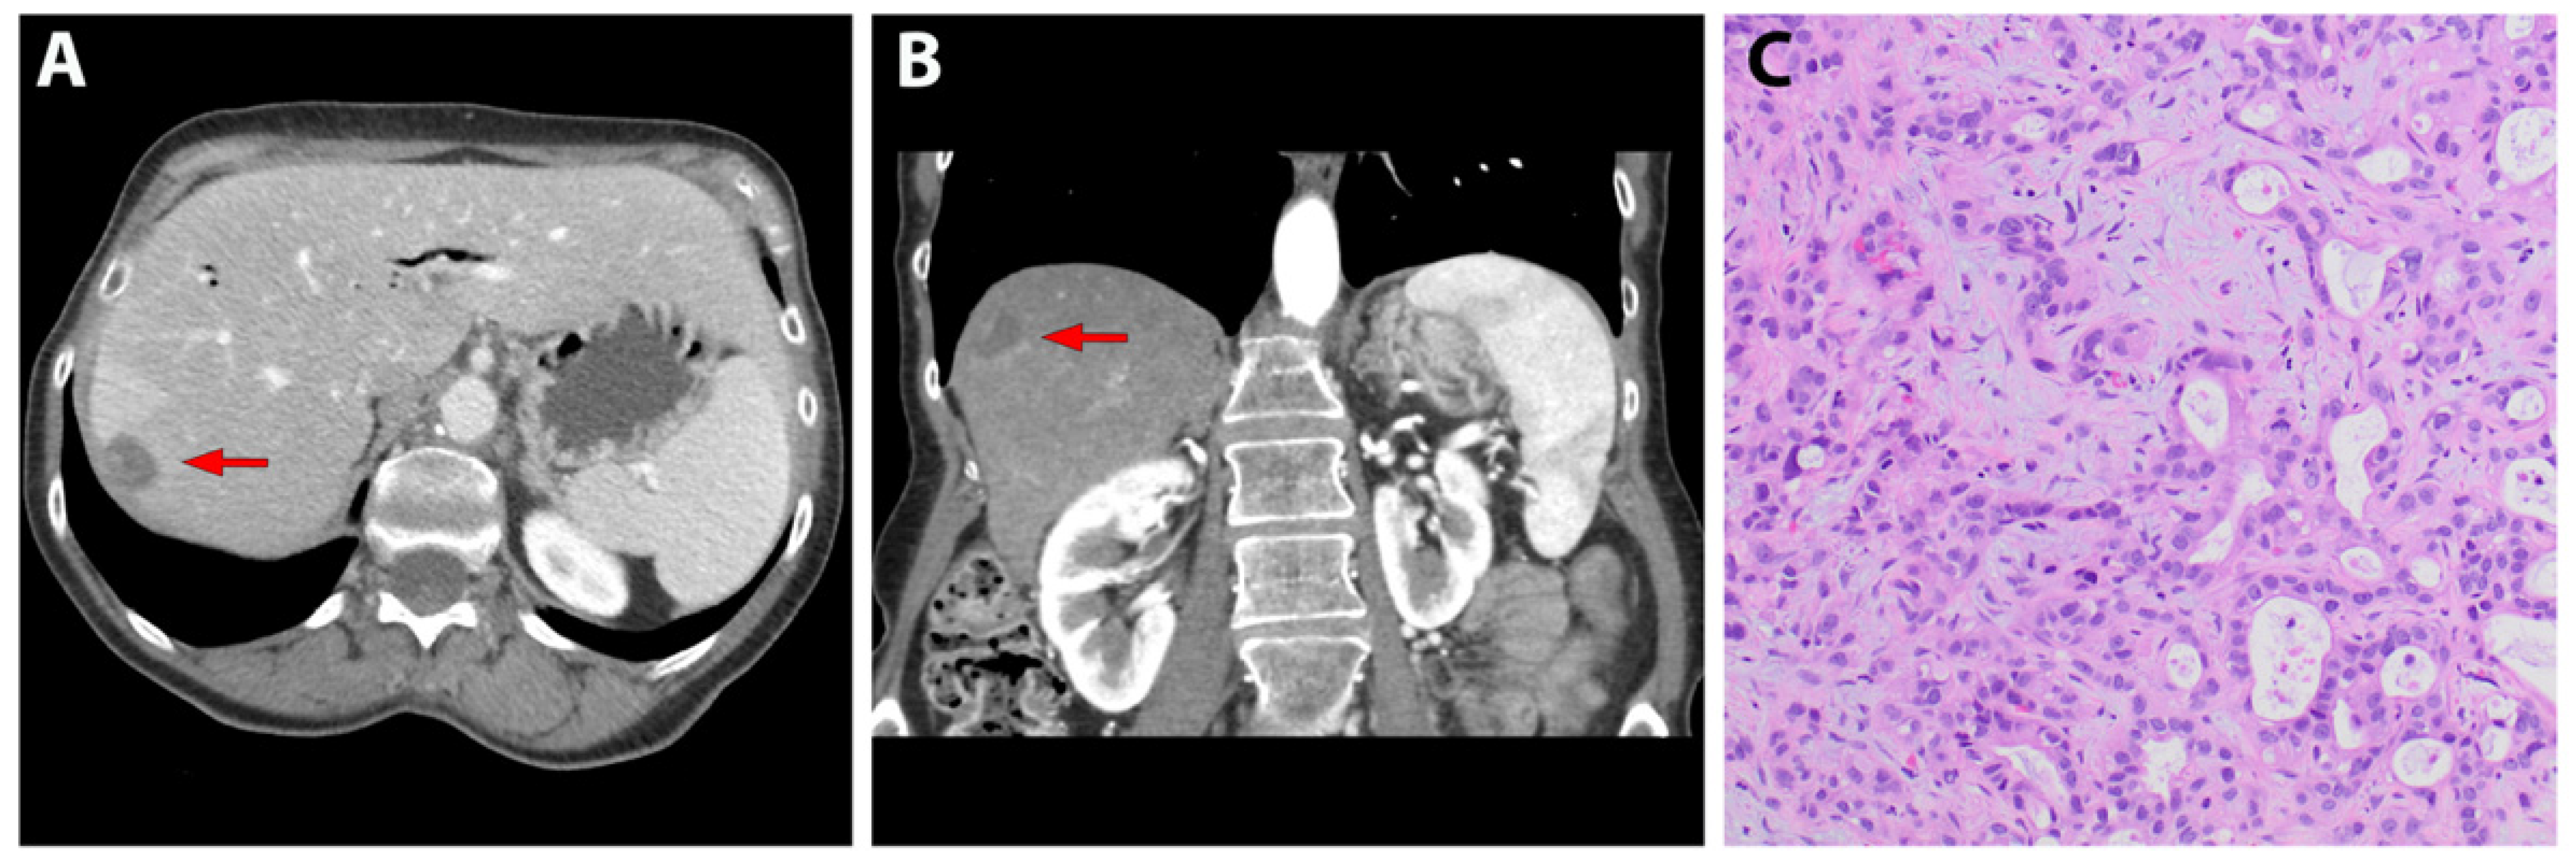

Pancreatic Cancer with Liver Metastases Pancreas Case Studies Liver Enzymes With Pancreatic Cancer persistently elevated liver enzymes may be caused by certain types of cancer, including liver, colon, breast,. The main primary sites of metastatic liver cancer for our patients are lung and brunchu, sigmoid. The pancreas lies behind the. Recent advances in surgical technique and. in addition, some liver and pancreas disorders increase your risk for more serious liver and. Liver Enzymes With Pancreatic Cancer.

Infiltrating Pancreatic Cancer with Liver Metastases Pancreas Case Liver Enzymes With Pancreatic Cancer the liver metastasis of pancreatic cancer is a multistage and multistep process. pancreatic cancer is a type of cancer that begins as a growth of cells in the pancreas. The main primary sites of metastatic liver cancer for our patients are lung and brunchu, sigmoid. feasibility of liver resection combined with pancreatectomy for pdac liver metastases. . Liver Enzymes With Pancreatic Cancer.